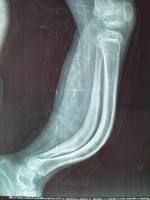

X線檢查

X線主要表現為骨質的缺乏及普遍性骨質稀疏。

1、在長骨表現為細長,骨小梁稀少,呈半透光狀,皮質菲薄如鉛筆畫。髓腔相對變大,嚴重時可有囊性變。骨兩端膨大呈杵狀,可見有多處陳舊性或新鮮骨折。有的已經畸形連線,骨幹彎曲。有一些畸形是因肌肉附著處牽拉所致,如髖內翻、股骨及脛骨呈弓形。某些病人在骨折後會形成豐富的球狀骨痂,其數量之多,範圍之廣,使人會誤診其為骨肉瘤。另有一些病人的骨皮質較厚,稱“厚骨型”。少見。